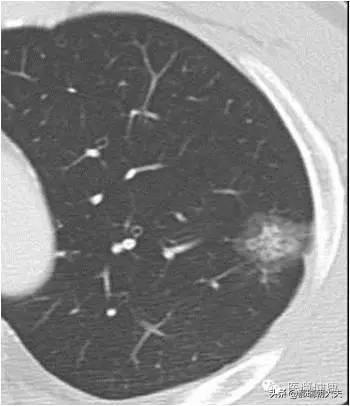

Les examens médicaux étant de plus en plus fréquents, les nodules pulmonaires sont de plus en plus souvent détectés. Les nodules pulmonaires sont un terme d'imagerie, et la définition d'imagerie d'un nodule pulmonaire est une petite lésion bien définie qui est complètement entourée par le parenchyme pulmonaire (Diamètre ≤30mm). La morphologie des nodules est classée comme solide ou sub-solide ; les nodules sub-solides sont eux-mêmes classés en nodules de verre dépoli et en nodules partiellement solides. Les lésions de plus de 30 mm de diamètre sont des masses plutôt que des nodules et ont une probabilité plus élevée d'être malignes.

Il existe des termes spécifiques pour désigner la taille des nodules pulmonaires : ceux dont le diamètre est ≤3cm sont appelés nodules et ceux dont le diamètre est supérieur à 3cm sont appelés masses ; plus le diamètre du nodule est important, plus le risque de malignité est élevé.